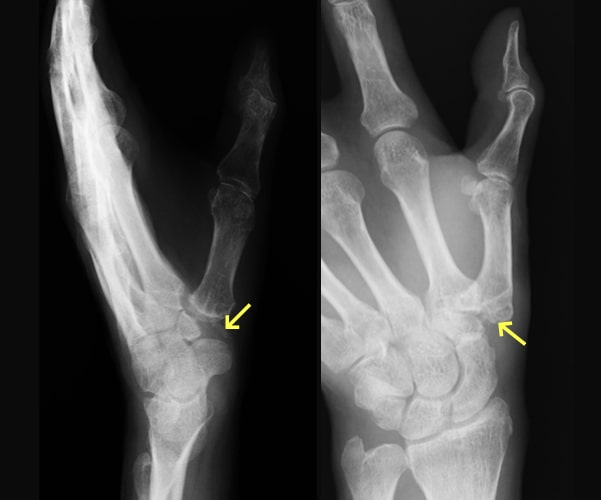

舟状骨骨折

舟状骨骨折写真

舟状骨骨折後偽関節

舟状骨骨折術後写真

骨移植併用内固定術後

原因

スポーツや事故で手をついて転倒することで生じます。舟状骨骨折は通常のレントゲン写真で分かりづらいことも多く、専門医でないと見落とすこともあります。手首の痛みが残る場合は舟状骨骨折を疑って多くの方向からレントゲン写真を撮ったり、CT撮影をする必要があります。

症状

腫れや痛みなどの症状が軽いため、整形外科への受診が遅れたり、手首の捻挫や打撲として診断されてしまっていることがあります。

治療方針

直後で骨折部のズレが少なければギプスで治療することも可能です。しかし、骨折部のズレが大きければ手術となります。また、長期間放置されて骨折部が治らないままとなったり(偽関節)、それに伴って関節の軟骨が摩耗した場合(変形性手関節症)は侵襲の大きな手術が必要となります。